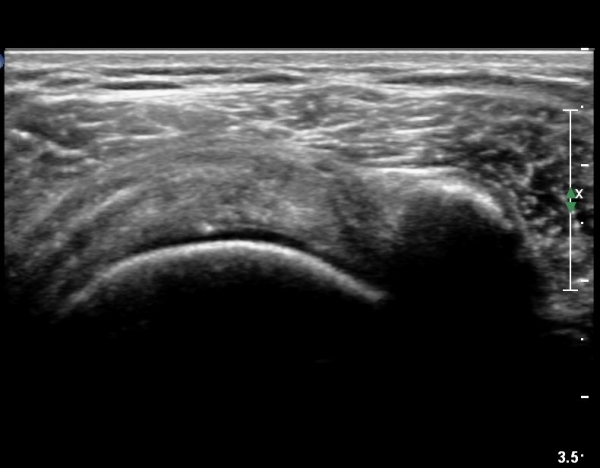

±Ø»ó°Ç Á¶´ã¸é°Ë»ç¿¡¼­ ±Ø»ó°ÇÀÇ ÅðÇ༺º¯È­È­ ºÎºÐÀûÀÎ ÆÄ¿­ÀÌ  °üÂûµÇ¸é ´ë°áÀýÀº

ºñÈĵǾî ÀÖ´Ù(»çÁø 6, 7, 8).